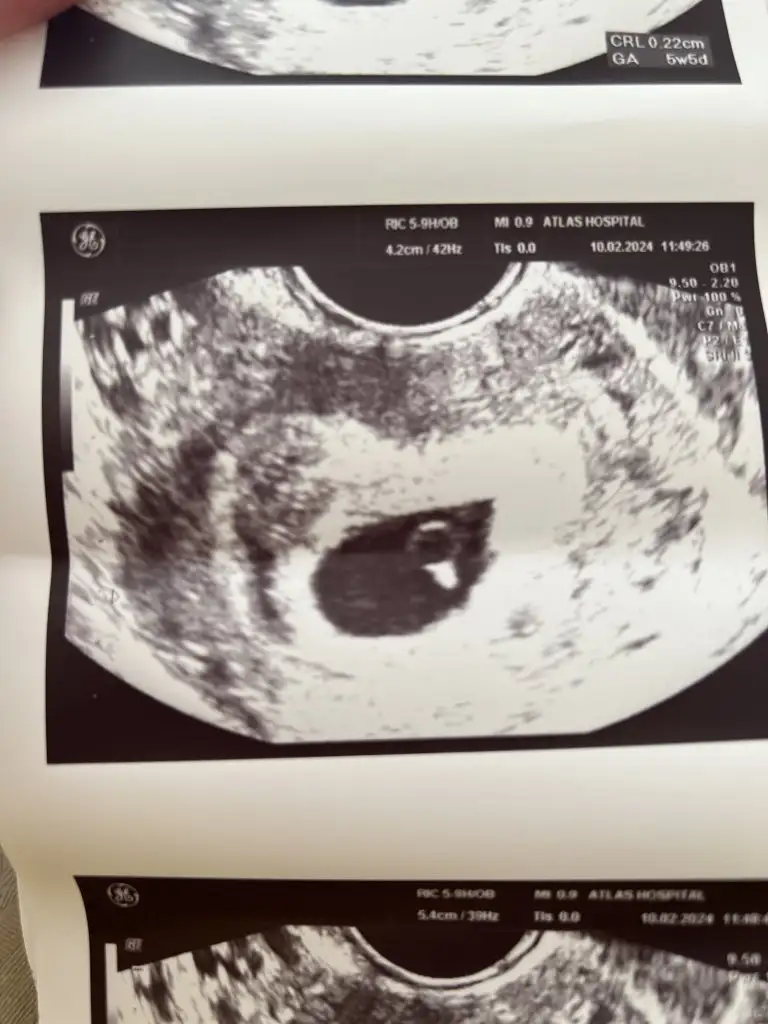

Cinsiyet tahmini

Selam bana da tahminde bulunabilir misiniz?

6haftalık vajinal ultrason